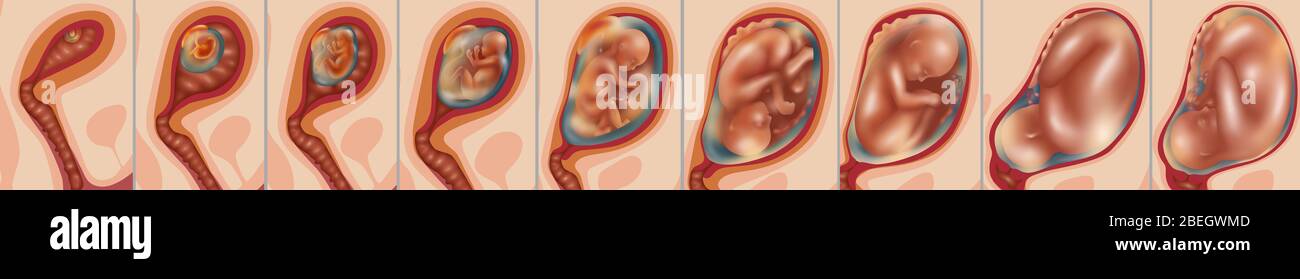

In addition to the information above, here is a curated collection of images related to Fetal Movements Hi Res Stock Photography And Images Alamy.

- Fetal Hi-Res Stock Photography And Images - Alamy

- 8,500+ Fetal Baby Stock Photos, Pictures & Royalty-Free Images - IStock